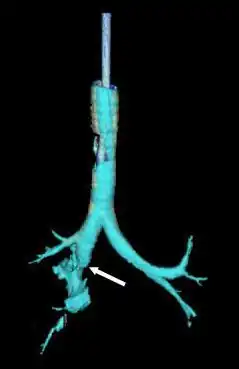

![]() Reconstrucción de la tráquea y los bronquios con tomografía computarizada de rayos X que muestra la interrupción del bronquio principal derecho con una elucidación anormal (flecha) | ||

El diagnóstico y el tratamiento rápidos son importantes en la atención de la LCT;[6] si la lesión no se diagnostica poco después de producirse, el riesgo de complicaciones es mayor.[11] La broncoscopia es el método más eficaz para diagnosticar, localizar y determinar la gravedad de la LCT,[6][10] y suele ser el único método que permite un diagnóstico definitivo.[23] El diagnóstico con un broncoscopio flexible, que permite visualizar directamente la lesión, es la técnica más rápida y fiable.[8] En personas con LCT, la broncoscopia puede revelar que la vía aérea está desgarrada, o que las vías respiratorias están obstruidas por sangre, o que un bronquio se ha colapsado, ocultando de la vista bronquios más distales (inferiores).[3]

La radiografía de tórax es la técnica de imagen inicial usada para diagnosticar la LCT.[17] La radiografía puede no tener ningún signo en un paciente por lo demás asintomático.[15] Las indicaciones de LCT vistas en las radiografías incluyen deformidad en la tráquea o un defecto en la pared traqueal.[17] La radiografía también puede mostrar enfisema cervical, aire en los tejidos del cuello.[2] Las radiografías también pueden mostrar lesiones y signos acompañantes como fracturas y enfisema subcutáneo.[2] Si se produce un enfisema subcutáneo y el hueso hioides aparece en una radiografía a una altura inusual en la garganta, puede ser un indicio de que la tráquea ha sido seccionada.[4] También se sospecha de LCT si un tubo endotraqueal aparece en una radiografía fuera de lugar, o si su manguito parece estar más lleno de lo normal o sobresale a través de un desgarro en las vías respiratorias.[17] Si se desgarra un bronquio en toda su extensión, el pulmón puede colapsarse hacia fuera, hacia la pared torácica (en lugar de hacia dentro, como suele ocurrir en el neumotórax), porque pierde la unión al bronquio que normalmente lo mantiene hacia el centro.[6] En una persona tumbada boca arriba, el pulmón se colapsa hacia el diafragma y la espalda.[23] Este signo, descrito en 1969, se denomina signo del pulmón caído y es patognomónico de LCT (es decir, es diagnóstico de LCT porque no se produce en otras afecciones); sin embargo, sólo se produce en raras ocasiones.[6] Hasta en uno de cada cinco casos, las personas con traumatismo contuso y LCT no presentan signos de la lesión en la radiografía de tórax.[23] La TC detecta más del 90% de los TLC resultantes de traumatismo contuso,[3] pero ni la radiografía ni la TC sustituyen a la broncoscopia.[6]